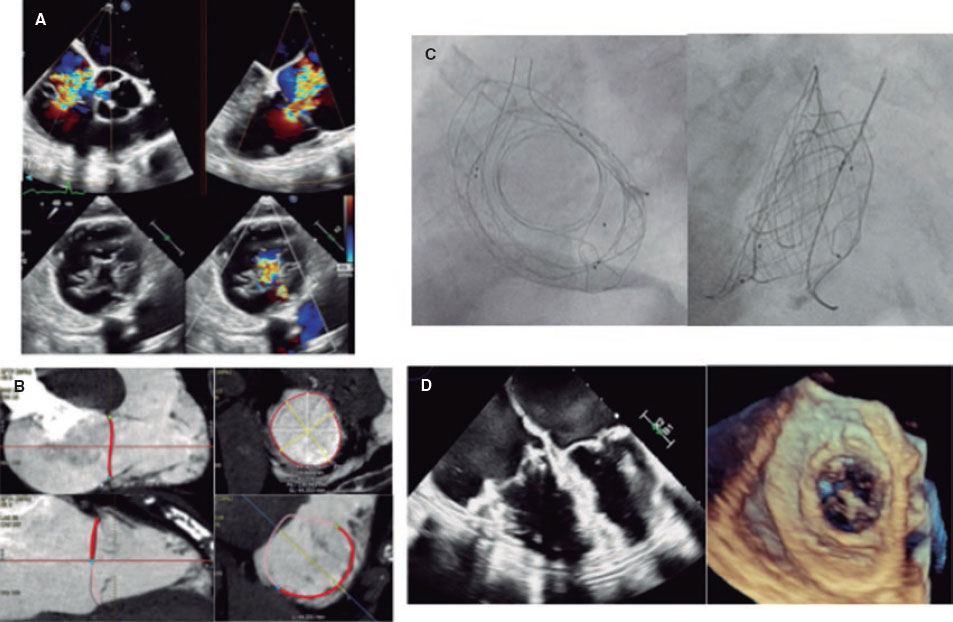

El procedimiento se realizó en una mujer de 81 años (TRI-SCORE 6), sintomática (clase IV de la New York Heart Association, ambulatoria) con insuficiencia tricuspídea masiva funcional (anchura del defecto de 9 mm) y anillo de 137 mm de perímetro (figura 2A-B). Se implantó una prótesis VDyne (tamaño 1 con sobredimensión del 6%) bajo guía fluoroscópica y ecocardiográfica, logrando una resolución completa de la insuficiencia tricuspídea detectada en las imágenes angiográficas, ecocardiográficas y de tomografía computarizada posprocedimiento (figura 2C-D y vídeo S1, vídeo S2, vídeo S3 y vídeo S4). Tras el alta hospitalaria al quinto día, la paciente presentó mejoría de la clase funcional (II), con mayor distancia recorrida en la prueba de la marcha (+90 m). Este caso refuerza el potencial del RVTP con prótesis específicas en pacientes sin alternativas previas.

Figura 2.